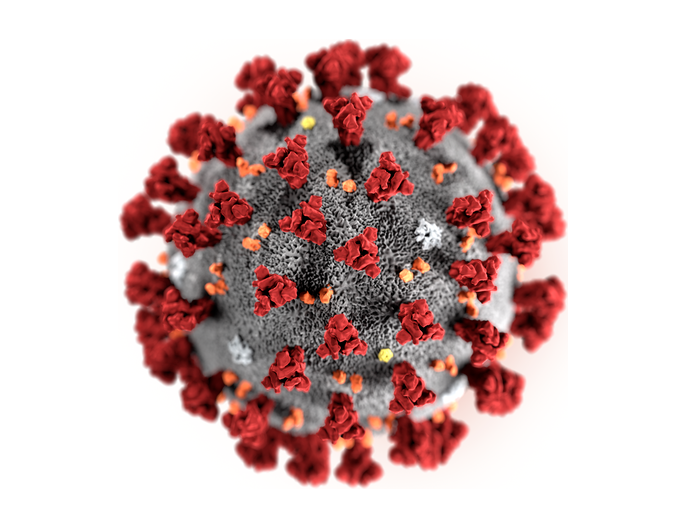

Noch Wochen und Monate nach einer Erkrankung an COVID-19 können gesundheitliche Langzeitfolgen bestehen. Welche Symptome treten bei Long COVID auf?…